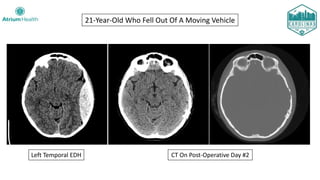

Case #2

15-year-old male brought into the ED by his parents after he sustained an

un-helmeted fall off of his skateboard.

History:

• Somnolent and confused

• Brief seizure as parents were putting him in the car to come to the ED

• Additional seizure in route with EMS, now combative and post-ictal

Primary and Secondary Survey:

• Tachycardic with normal blood pressure and oxygen saturations

• Scalp hematoma on physical exam

• Initial GCS 12 (E4, V3, M5)... declined to GCS 9 (E2, V3, M4)

• Patient seized again in the ED and was promptly intubated

15-Year-Old Struck His Head Skateboarding

15-year-old male brought into the ED by his parents after un-helmeted fall

off skateboard.

Clinical Course:

• Taken to Operating Room with neurosurgery for craniotomy

• Uncomplicated post-operative course

• Discharged on post-operative Day #3 with a prescription for levetiracetam

• Seen by pediatric neurology at 1.5 months, no further seizures

• Plan for discontinuation of antiepileptics if a 6-month EEG is negative

• Unfortunately, the patient was lost to follow up